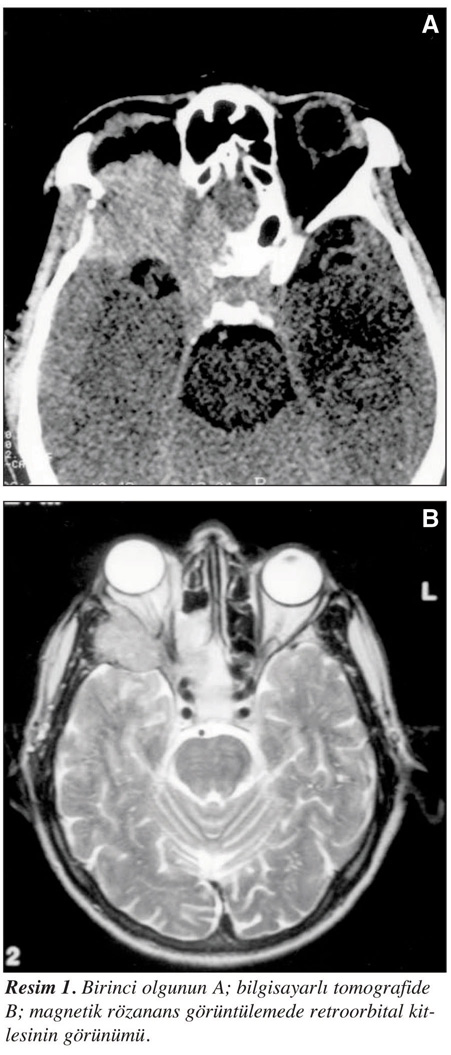

Elli yaşındaki erkek hasta baş ağrısı ve bulanık görme yakınması ile hastaneye başvurdu. Daha önce hafif olan ağrıları son iki haftadan beri artmıştı. Hastanın hipertansiyonu vardı ve antihipertansif tedavi kullanıyordu. Soygeçmişinde ve sistem sorgulamasında özellik yoktu. Hastanın kan basıncı 150/85 mm/Hg, ateş 36.8°C, nabız 78/dakika, solunum sayısı 16/dakika idi. Hastanın bilinci açık ve koopere idi [performans statusu 1 (ECOG)]. Fizik muayenesinde sağ gözde hafif şişlik vardı ve aşağı bakış sınırlı idi. Diğer sistemler normaldi. Lökosit 11.2 x 109/L, hemoglobin 11.3 g/dL, hemaktokrit %37.6, trombosit 244 x 109/L, BUN 28 mg/dL, açlık kan şekeri 77 mg/dL, Na 143 mEq/L, total bilirubin 0.9 mg/dL AST 16 IU/L, ALT 11 IU/L, GGT 77 IU/L, LDH 513 IU/L, kreatinin 1.4 mg/dL, Ca 8.6 mg/L, total protein 7.2 g/dL, albumin 3.8 g/dL, ürik asit 6.2 mg/dL bulundu. Posteroanterior (PA) akciğer grafisi ve iki yönlü kafa grafisi normaldi. Hastanın bilgisayarlı beyin tomografisinde (BBT) sağ orbita arka duvarını ve sağ sfenoid kanadı deksrükte eden kavernöz sinüslere infiltre intrakranial kitle saptandı (Resim 1). Kraniotomi ile kitleye ulaşıldı ve subtotal kitle eksizyonu yapıldı. Patolojik incelemede tümörün plazma hücrelerinden oluştuğu ve kappa antikorlarıyla yaygın olarak pozitif boyandığı görüldü (Resim 2). Hastanın protein elektroforezinde beta bandında monoklonal pik saptandı (Şekil 1). Kappa 944 mg/dL (200-440), lambda 59.8 mg/dL (110-240), Ig G 640 mg/dL (850-1220), Ig A 884 mg/dL (130-227), Ig M 18.3 mg/dL (52-125) olarak bulundu. Bence-jones proteinürisi yoktu. Hastanın kemik iliği aspirasyonunda plazma hücre oranı %10’un altında saptandı. Hastaya kranial radyoterapi planlandı, ancak gözü riske etmemek için başlanılmadı. Hastanın LINAC uygulanan bir merkeze gitmesi sosyoekonomik nedenlerden dolayı mümkün olmadı. Hastaya siklofosfamid, melfelan ve prednizolondan oluşan kemoterapi başlandı. Hasta radyoterapi için bekler ve kemoterapisi devam ederken 4. ayda lokal nüks gelişti. Hastada bilateral görme kaybı vardı. İkinci bir cerrahi girişim yapılamadı. Acil kranial radyoterapi başlandı. Hastada monoklonal protein sekresyonu hala devam ediyordu. Kemik iliğinde plazma hücre oranı %5’in altındaydı. Hasta takibinin 6. ayında genel durumu bozularak kaybedildi.